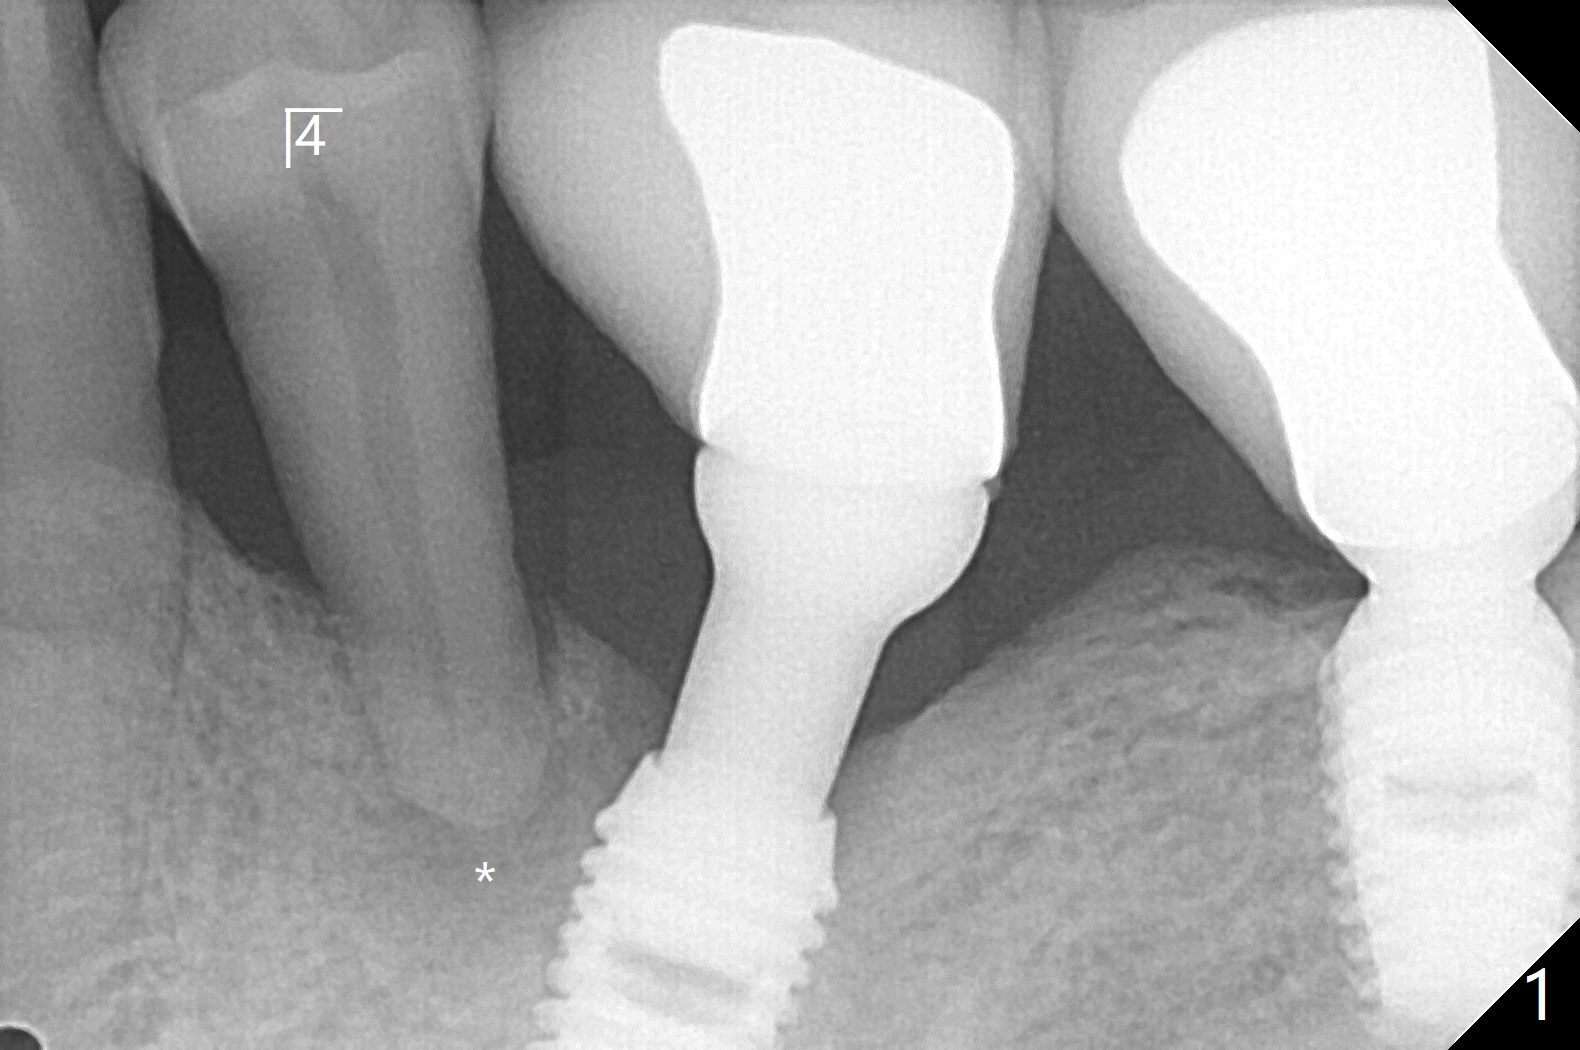

52岁男右下4植体脱落,植骨后,使用左侧咀嚼,发现左下4松动(图一,二),无法吃饭,认为必须拔除植牙(图三,四),徒手种植的邻近植体位置不好,但无骨质吸收(图五,六(牙冠粘固后9年10月)),4种植必须用导板